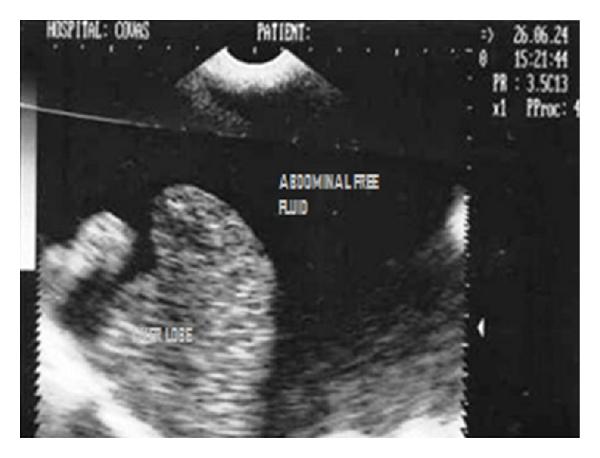

Hepatic disease is often treatable and has a predictable prognosis when a definitive diagnosis is made. The aim of clinicopathological evaluation of hepatobiliary affections is to identify and characterize hepatic damage and dysfunction, identify possible primary causes of secondary liver disease, differentiate causes of icterus, evaluate potential anaesthetic risks, assess prognosis and response to xenobiotics, and monitor response to therapy. This paper describes the different diagnostic methods and imaging techniques employed in diagnosis of hepatobiliary affections in dogs. Besides reviewing the significant clinical manifestations and imaging structural abnormalities in diagnostic approach to different hepatic affections, it also depicts radiographic, ultrasonographic, and wherever applicable, the laparoscopic characterization of different hepatic affections and target lesions encountered in clinical cases presented in the Teaching Veterinary Clinical Complex, COVAS, Palampur in the year 2007-2008.

肝病通常是可治疗的,一旦做出明确诊断,其预后是可预测的。肝胆疾病临床病理评估的目的是识别和描述肝损伤及功能障碍,确定继发性肝病可能的主要病因,鉴别黄疸的病因,评估潜在的麻醉风险,评估预后及对外源化学物质的反应,并监测治疗反应。本文描述了用于诊断犬肝胆疾病的不同诊断方法和成像技术。除了回顾不同肝病诊断方法中的重要临床表现和成像结构异常外,还描述了2007 - 2008年在帕兰普尔兽医临床综合教学中心(COVAS)出现的临床病例中不同肝病及目标病变的放射学、超声学特征,以及在适用情况下的腹腔镜特征。